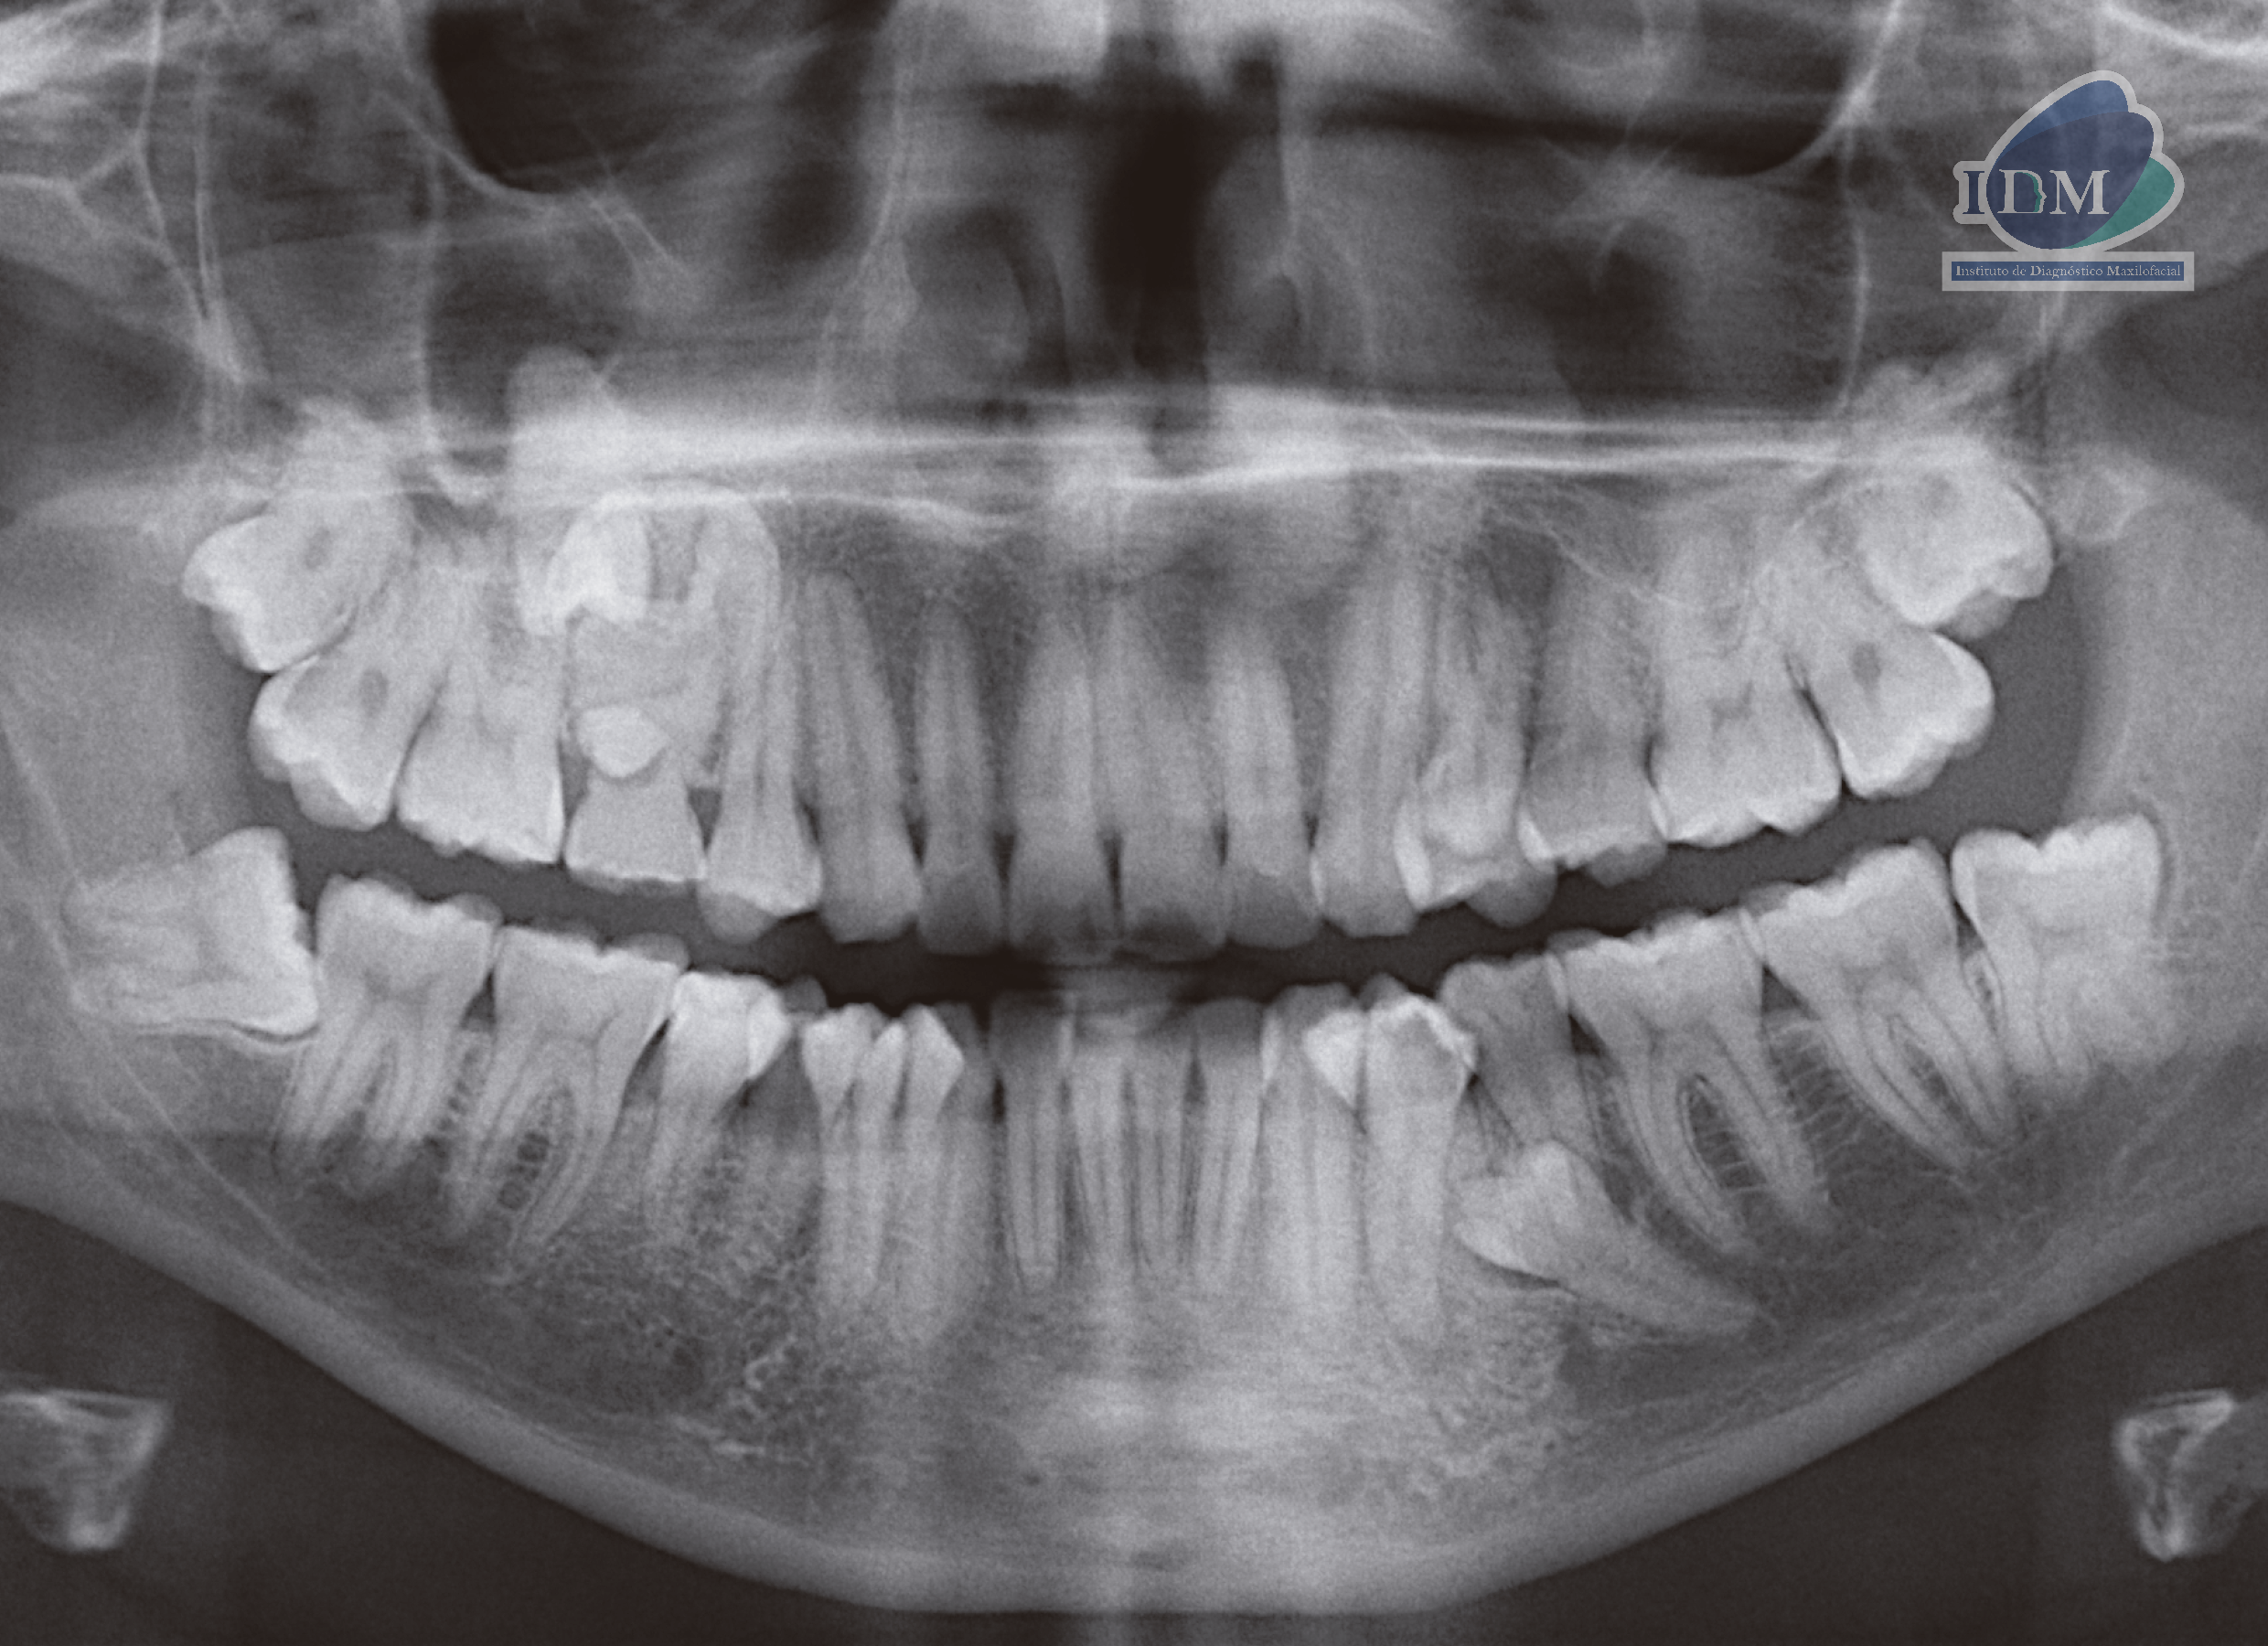

En la radiografía panorámica (Figura 1), se aprecia pieza supernumeraria proyectada entre pieza 55 y pieza supernumeraria 2, imagen radiopaca de densidad dentaria proyectada sobre zona de pieza 15, de limites definidos y forma irregular.

Radiografia Panorámica